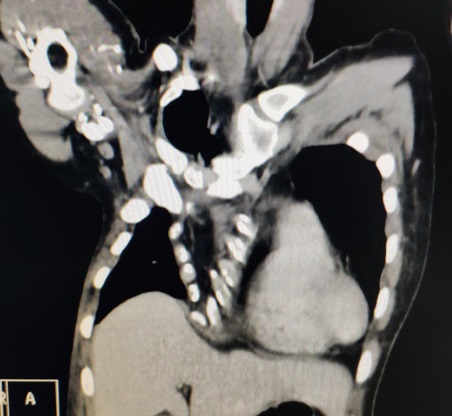

X线检查:正位片见心脏左偏,位于左侧胸腔,左侧肋骨走向异常;侧位片见前胸壁明显畸形。CT检查:前胸壁不对称、不规则型凹陷,凹陷最低处低于脊柱前沿。心脏受压,右侧胸廓严重变形(图1-2)。三维重建:前胸壁极度变形,呈不规则、不对称型凹陷。胸骨体受累,右侧胸壁结构变形严重(图4-6)。

图4,三维重建图提示重度畸形。

图5,三维重建图显示,凹陷最底部低于脊柱前缘,Haller指数无法测得。

图6,三维重建图显示胸廓正常形状消失。